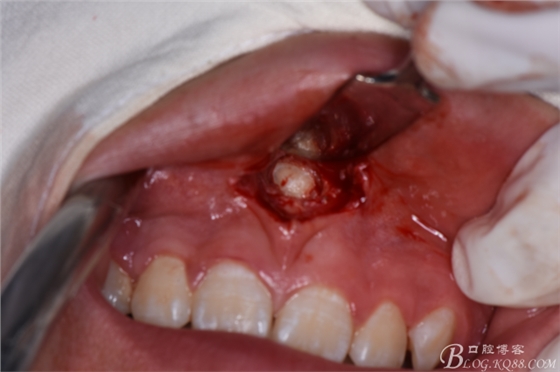

圖8.先拔除11、21之間多生牙,做唇側(cè)弧形切口

圖9.翻瓣、暴露唇側(cè)骨面,高速渦輪機去骨。

圖10.暴露出11、21之間的倒置多生牙牙冠